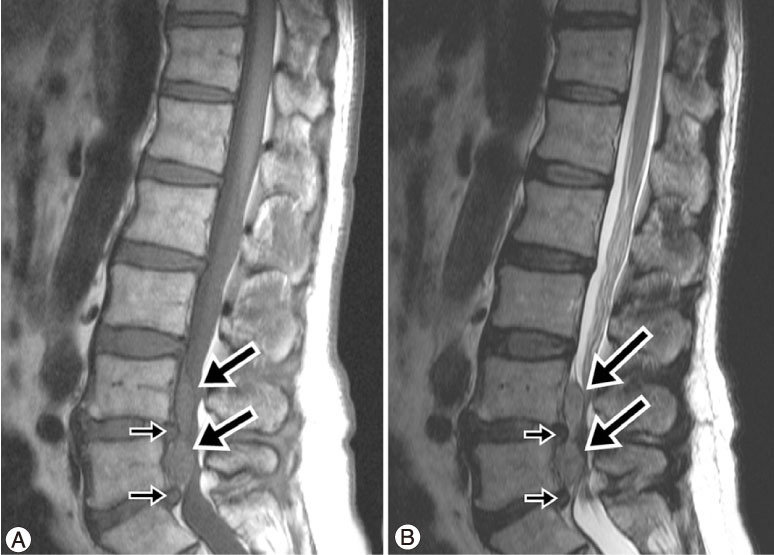

Spondylolisthesis

Jongedame (18) met pijn in de rug voelbaar trapje op L5 en krachtverlies in beide benen

Beeldvorming

• NHG (2015) NA 6 weken in samenspraak met patiënt2

Wanneer OPereren?

• NIET bij klachten < 6 weken

• NIET WANNEER PIJN DE ENIGE KLACHT IS

• ​NIET WANNEER HET DERMATOOM NIET OVEREENKOMT MET DE BEKNELDE ZENUW

• WEL tussen 3 maanden en 6 maanden

• Wel bij ernstige of progressieve verlamming of verlies van blaasfunctie

• Mogelijk Bij patiënten die bedlegerig blijven ondanks medicatie